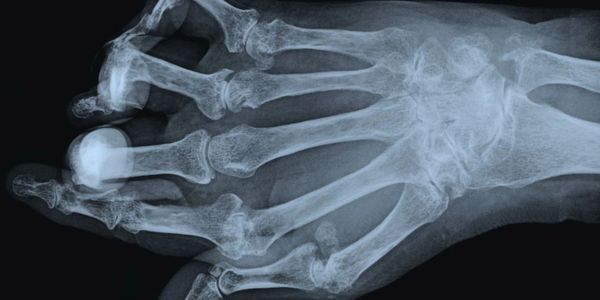

Common symptoms of arthritis joint diseases include swelling, stiffness, pain and decreased ROM (range of motion). Symptoms can come and go; they can be mild, moderate or severe; symptoms can be mild for years and and then suddenly intensify and get worse over time. Severe arthritis can produce chronic pain, inability to complete simple daily tasks and make it challenging to even walk or go upstairs and can cause permanent joint variations. These changes can be noticeable and demonstrate visible signs such as knobby finger joints. Sometimes the joint damage can only be seen on X-ray. Some forms of arthritis can also affect the heart, eyes, lungs, kidneys and skin, in addition to someone’s joints.